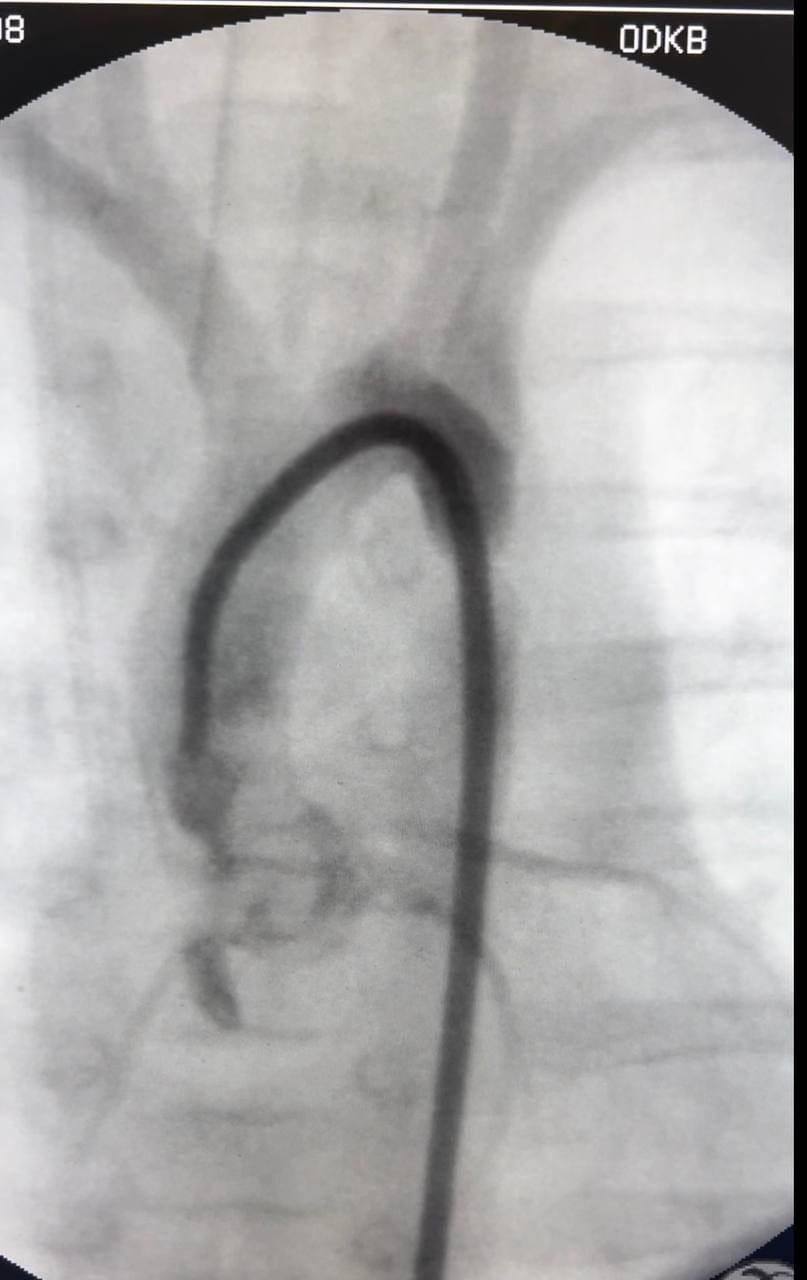

In Odessa, babies with heart defects underwent surgery

"In the first child, the open arterial duct was closed, and in the second, X-ray endovascular dilatation of coarctation of the aorta was performed," the doctors noted.

The babies survived the surgery well, they are now recovering and gaining weight.